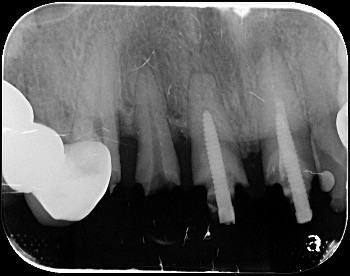

X光 / 斷層掃描

獲取病患口腔狀況

安適準導航植牙系統可以於植體製作前(術前)做第一次植牙流程規劃,判讀病患牙齒間狀況,並做出最合適的植牙療程建議。搭載高達12顆鏡頭,於手術間幾乎零死角定位植牙位置,配合AI高速運算,讓植體精準的植入齒骨,創造幾乎與原生牙齒無二的舒適感。

- AR實時成像,植入點寬度、深度毫釐不差

- 定位誤差小於0.2mm RMSE